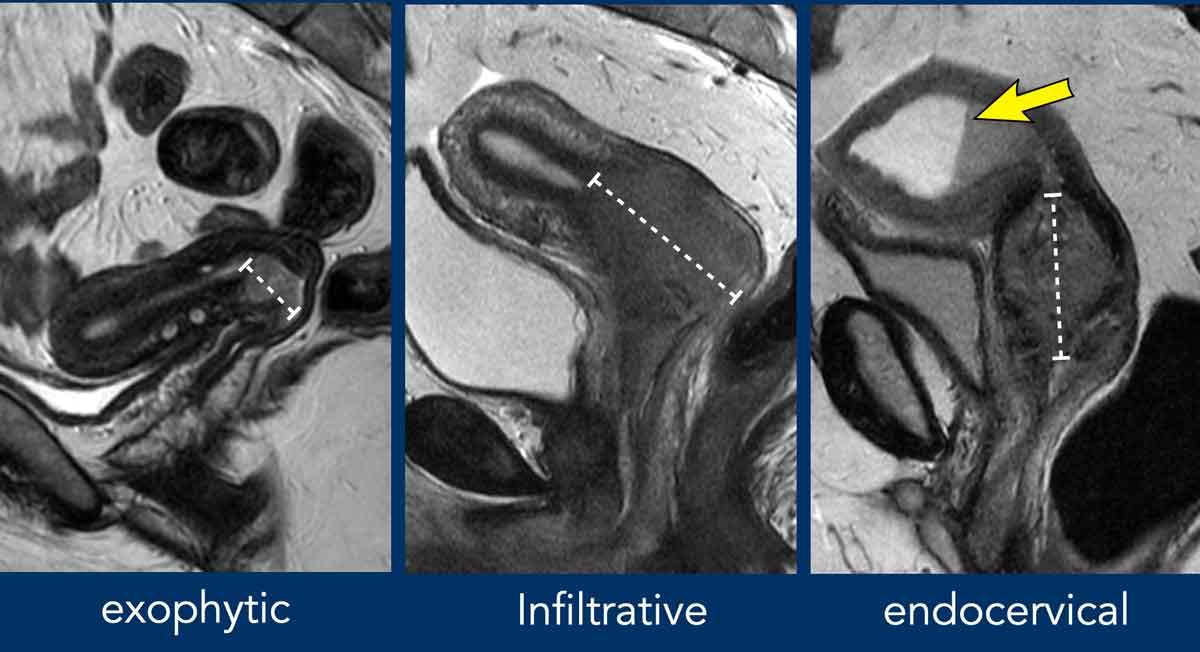

Kích thước khối u cần được đo theo chiều dài lớn nhất có thể, thường được quan sát rõ nhất trên mặt phẳng đứng dọc và đôi khi trên mặt phẳng đứng ngang.

Các khối u cổ tử cung có thể biểu hiện dạng phát triển ngoại sinh (thường gặp ở phụ nữ trẻ), thâm nhiễm lan tỏa hoặc nội cổ tử cung (thường gặp ở phụ nữ lớn tuổi hơn và/hoặc ung thư biểu mô tuyến).

Lưu ý rằng trong hình ảnh bên phải, nơi có khối nội cổ tử cung, khối này gây tắc nghẽn ống cổ tử cung với sự giãn rộng của buồng tử cung chứa đầy dịch tăng tín hiệu và máu đồng tín hiệu tạo thành đường phân cách dịch-máu.